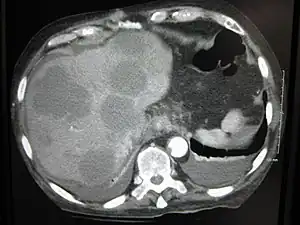

This is typical route of metastasis for sarcomas, but it is also the favored route for certain types of carcinoma, such as renal cell carcinoma originating in the kidney and follicular carcinomas of the thyroid. Because of their thinner walls, veins are more frequently invaded than are arteries, and metastasis tends to follow the pattern of venous flow. That is, hematogenous spread often follows distinct patterns depending on the location of the primary tumor. For example, colorectal cancer spreads primarily through the portal vein to the liver.